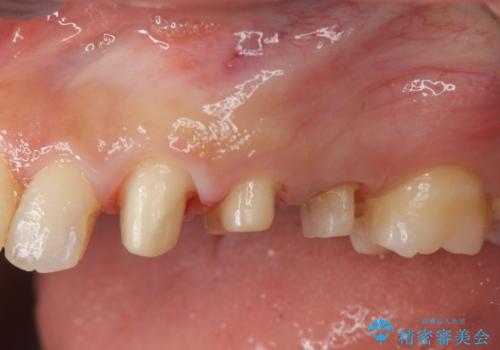

挺出小矯正を行った縁下カリエス治療

- 治療途中で虫歯治療を放置し、違和感が強くなってきたためしっかりとした虫歯治療を行いたいと希望され来院されました。

X線撮影を行い、隣接面に多発した虫歯と歯ぐきよりも深くなってしまった虫歯を小矯正をおこなったのちのセラミック治療で問題を解決します。